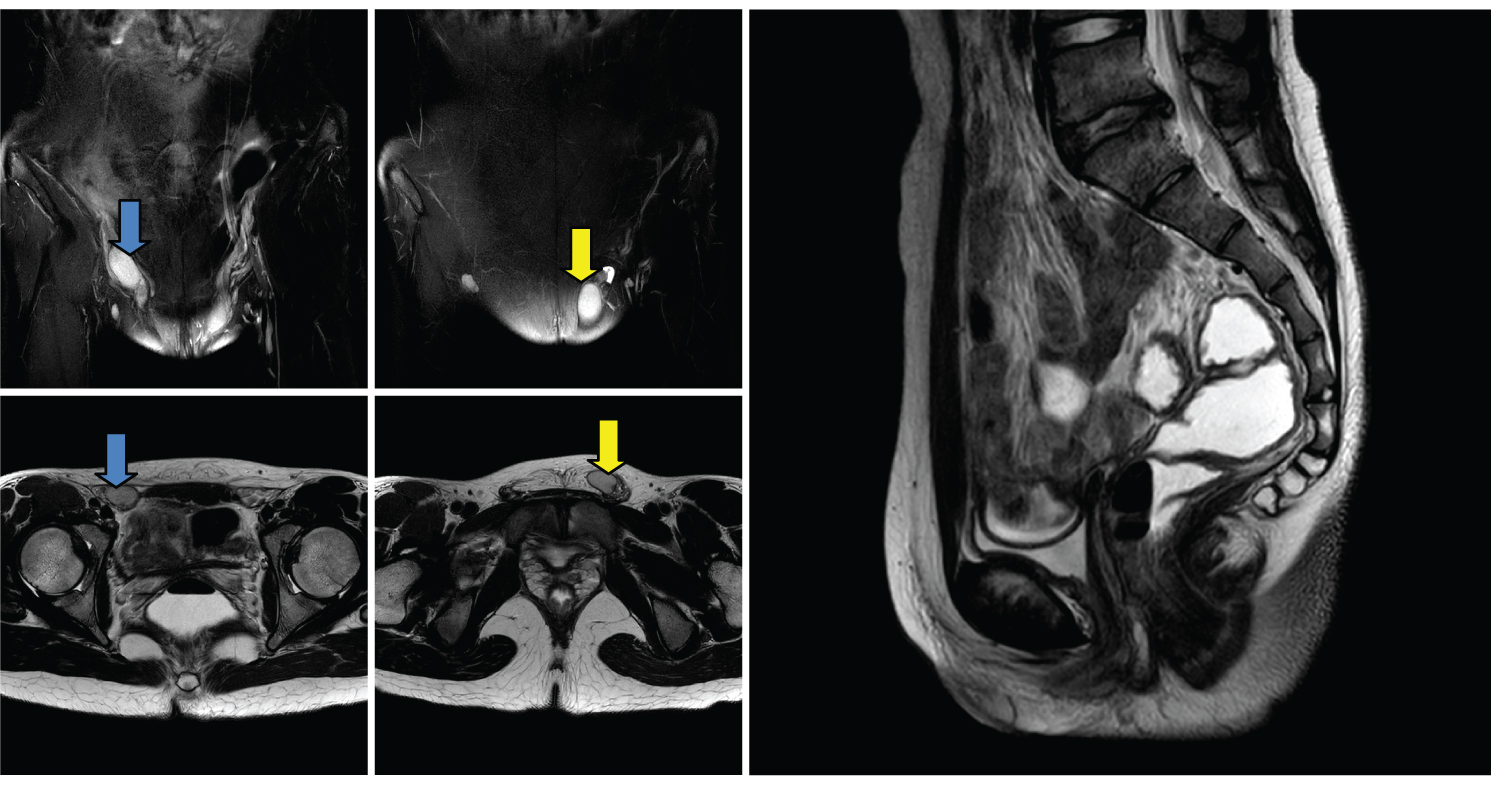

Hormone tests were shown as Table 1. Pelvic MRI (Figure 1) showed absence of prostate, seminal vesicles, uterus or ovary, and there was a testis on each side of the pudendal area. Male pseudohermaphroditism was considered. Karyotype test was done in the other hospital showing 47, XXY (12)/46, XY (88) mosaicism. It was a pity that DNA analysis for AR gene mutations was unavailable.

Figure 1: MRI ABDOMEN PELVIS t2 weighted showing the testicles annotated by blue (right side) and orange (left side) arrow (coronal and axial cuts) and complete absence of prostate, uterus, cervix and internal vagina (sagittal cut). View Figure 1